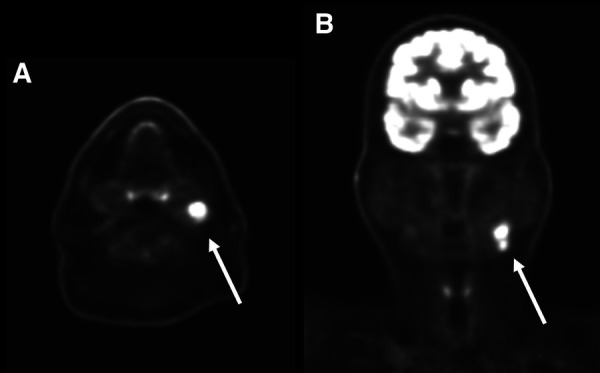

Abstract Image